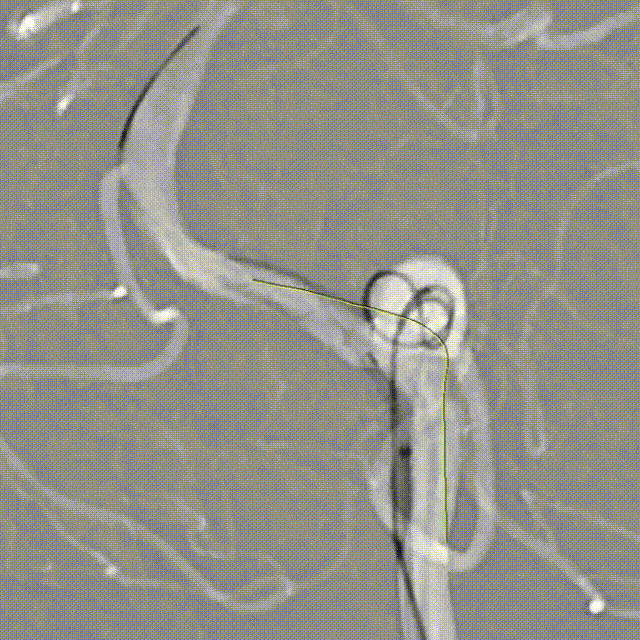

Tubridge Plus Case 2